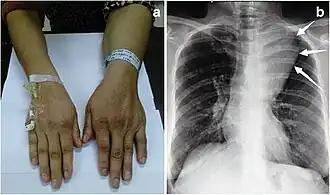

O angiolipoma geralmente se manifesta como muitos nódulos subcutâneos dolorosos (solitários em apenas um terço dos pacientes), mais comumente originados nos membros superiores (dos quais o antebraço representa cerca de dois terços), no tronco e nos membros inferiores.[3][4] Essas lesões são bem definidas, geralmente medindo menos de 4 cm.[5]

- ↑ Hassan, Hunar A.; Hassan, Hemn A.; Ali, Rebwar A.; Omar, Diyar A.; Salih, Abdulwahid M.; Kakamad, Fahmi H. (2022). «Multiple angiolipoma of the hand, back, and abdomen; a case report». Elsevier BV. International Journal of Surgery Case Reports. 93: 106901. ISSN 2210-2612. PMC 8927707

. PMID 35298986. doi:10.1016/j.ijscr.2022.106901